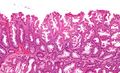

Intermediate magnification micrograph of a SSA.